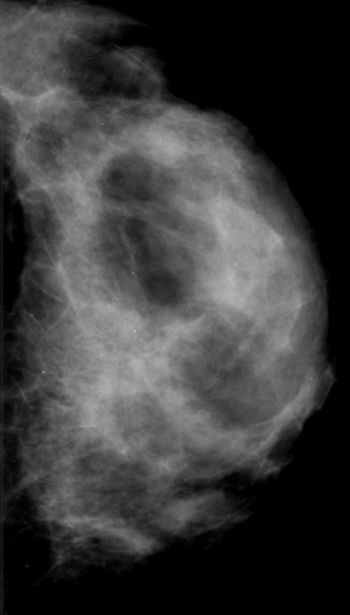

49-year-old patient presented for bilateral screening mammogram as well as bilateral screening ultrasound due to dense breast tissue.